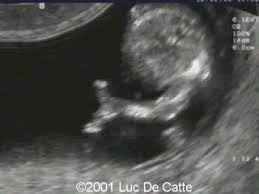

4.) Ectrodactyly

Ectrodactyly, or Split Hand/Split Foot Malformation, is the clefting of the hands or feet due to the lack of development of the middle fingers/toes.

It can either present unilaterally (one hand/foot affected) or bilaterally (both hands/feet affected). While ectrodactyly can affect both the hands and the feet, it is most popularized as “lobster hands”, associated with 19th-century circus “freak” shows.

On ultrasound, the splitting of the hands and feet can be visualized and diagnosable. While it can be isolated, syndromic indications might include cleft lip/palate and heart defects, so those areas are evaluated as well.

(In the case I scanned, it presented in the hands bilaterally).